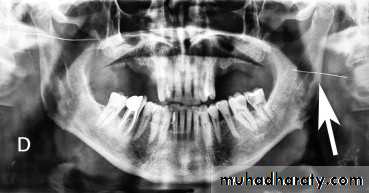

Management of retained needles requires locating the broken fragment through panoramic, computed tomographic (CT) scan or CBCT. The treatment options should be discussed with the patients. Retrieval usually is performed under general anesthesia. For broken needles embedded in the pterygo-mandibular space an intraoral approach through a vertical incision along the anterior border of the mandible,

15

extending inferiorly to the external oblique ridge, followed by sub-periosteal dissection along the medial aspect of the ramus of the mandible to identify bony landmarks (lingula), which can be used as

reference during exploration and also provides greater protection to the inferior alveolar and lingual nerves, supra-periosteal blunt dissection may be needed to identify the needle.